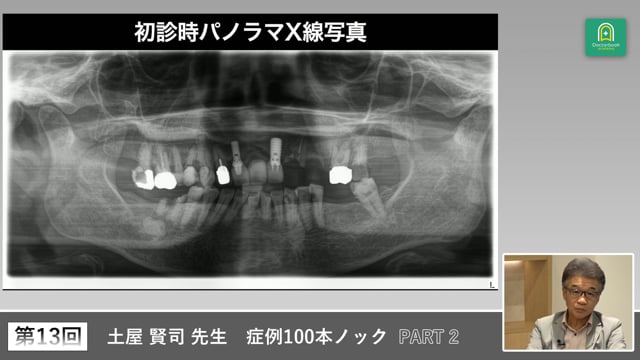

適切な治療計画にはバックグラウンドの把握が必要です。なぜ歯を失ったのか。パノラマ写真や口腔内写真からわかることは多くあります。どこに目を付ければ何が分かるのでしょうか?土屋先生と考えていきましょう。